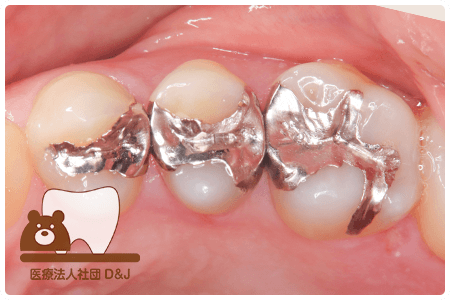

症例8フルジルコニアクラウン

治療前

治療中

治療後

治療前

治療中

治療後

29歳 女性

- 治療内容

- 銀歯からフルジルコニアクラウンへの修復

- 治療期間

- 根の治療含め3か月

- 費用

- 自費

フルジルコニアクラウン:77,000円(税込)

- その他の治療の費用は含まれておりません。

- リスク・副作用

- 強い衝撃が加わると欠けたり割れたりする可能性があります。また、噛み合わせの状態によっては脱離や周囲の歯への影響が出ることもあります。